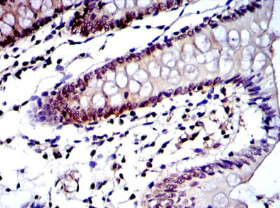

PSMB8 Mouse Monoclonal antibody[1A5H2]

The proteasome is a multicatalytic proteinase complex with a highly ordered ring-shaped 20S core structure. The core structure is composed of 4 rings of 28 non-identical subunits; 2 rings are composed of 7 alpha subunits and 2 rings are composed of 7 beta subunits. Proteasomes are distributed throughout eukaryotic cells at a high concentration and cleave peptides in an ATP/ubiquitin-dependent process in a non-lysosomal pathway. An essential function of a modified proteasome, the immunoproteasome, is the processing of class I MHC peptides. This gene encodes a member of the proteasome B-type family, also known as the T1B family, that is a 20S core beta subunit. This gene is located in the class II region of the MHC (major histocompatibility complex). Expression of this gene is induced by gamma interferon and this gene product replaces catalytic subunit 3 (proteasome beta 5 subunit) in the immunoproteasome. Proteolytic processing is required to generate a mature subunit. Two alternative transcripts encoding two isoforms have been identified; both isoforms are processed to yield the same mature subunit.

Species Reactivity:    Human,Rat

IHC    1/200 - 1/1000